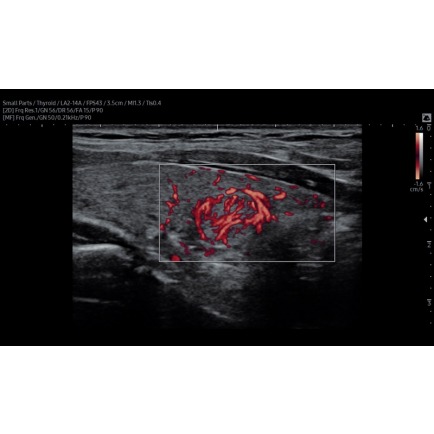

С помощью УЗИ Samsung Medison RS85 Prestige изображения получаются четкими и однородными, без зернистости и артефактов. Он позволяет проводить расширенные исследования сосудистой системы с качественным отображением интенсивности и объема кровотока. А с подключением энергетического допплера визуализируются даже периферические сосуды.

S-Detect for Thyroid – обнаруживает и классифицирует заболевания щитовидной железы.

Узел щитовидной железы в режиме MV-Flow, линейный датчик 2-14 МГц